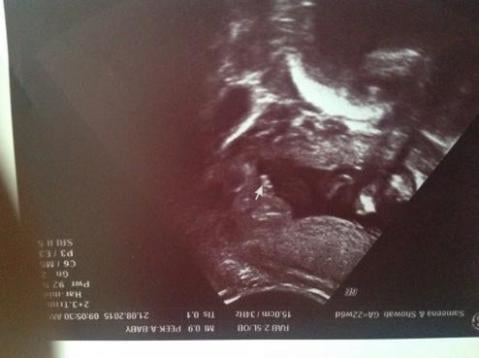

Hey guys please have a look at my scan pic I can see 3 lines and scotrum tech wasn't sure if G or BO

Girl.